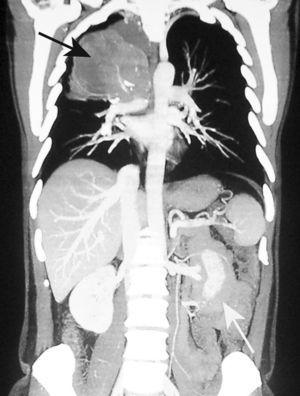

Fig. 2. Imagen de tomografía axial computarizada (TC), con contraste intravenoso, de los lóbulos inferiores(A), donde se observa una masa sólida cavitada en el lóbulo inferior derecho (flecha blanca). En la imagen de TC con contraste intravenoso de la cavidad abdominal inferior (B), se observan un engrosamiento de asas del intestino delgado (flecha blanca) y adenopa-tías mesentéricas (flecha negra), hallazgos en relación con metástasis de un carcinoma primitivo de pulmón de células grandes indiferenciado.